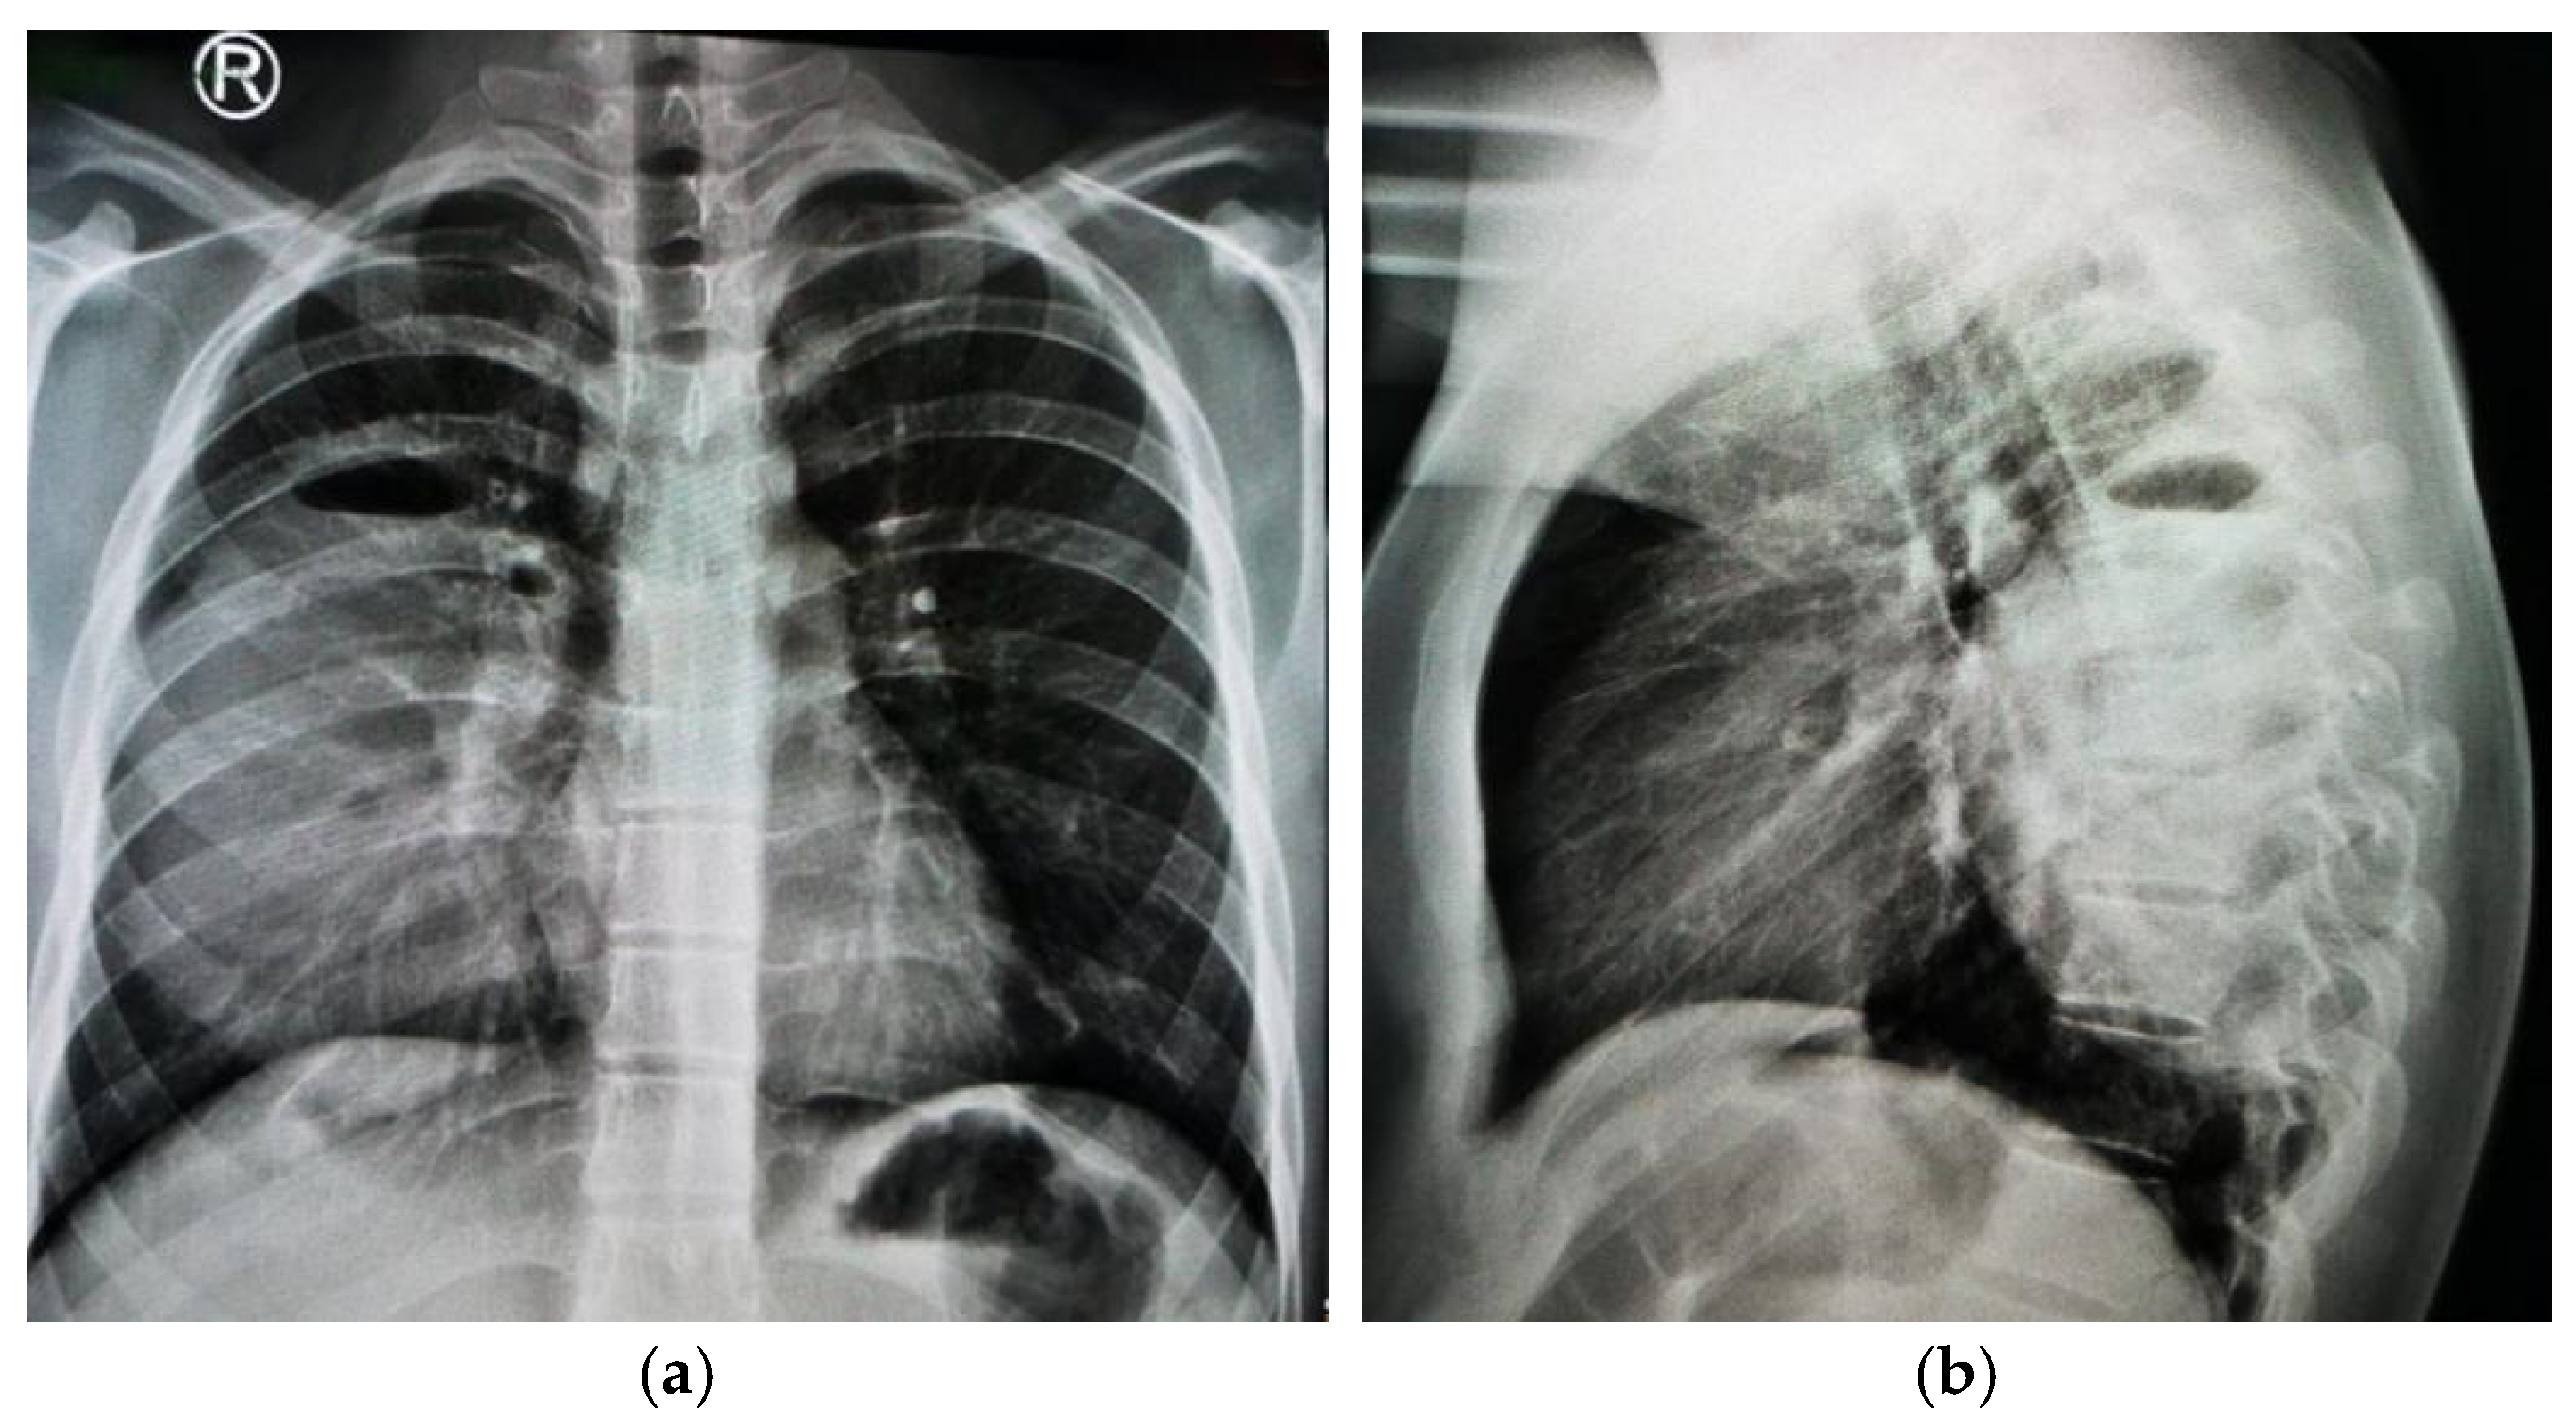

1.9.2. Case 2